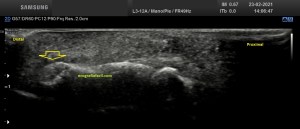

En este breve post te voy a presentar unas imágenes muy bonitas de una vesícula, en una paciente que acude a la cita de ecografía por sospecha de patología a ese nivel, con molestias anodinas e inespecíficas en el contexto de un estudio de su especialista de digestivo.

Observa las imágenes y luego te explico los hallazgos:

Cuando hice el corte longitudinal de la vesícula pude ver hasta tres patologías distintas, una adeomiomatosis (sin artefacto en cola de cometa), una litiasis vesicular y barro biliar, 2,3 y 4 respectivamente.

El caso no tiene mucho que explicar a no ser por la rareza de que se presente triple la semiología patológica en una misma imagen.

La adenomiomatosis, como un aumento de la ecogenicidad y el tamaño de la pared vesicular, la litiasis como una estructura hiperecogénica con sombra acústica posterior y el barro biliar, hiperecogénico rellenando toda la estructura ovoidea de la vesícula.

El cuello vesicular estaría afectado por la adenomiomatosis, el cuerpo por la litiasis y el barro ocuparía el fundas vesicular.

Para el estudio de la adenomiomatosis es obligado que el foco esté situado en la línea de interés, eso hará que las imágenes sean más nítidas y podamos estudiar dicha ecoarquitectura y su patología convenientemente.

Debemos observar si existiese líquido perivesicular, o signos de colecistitis. En este caso, la paciente, con estas tres patologías ya iba bien servida.